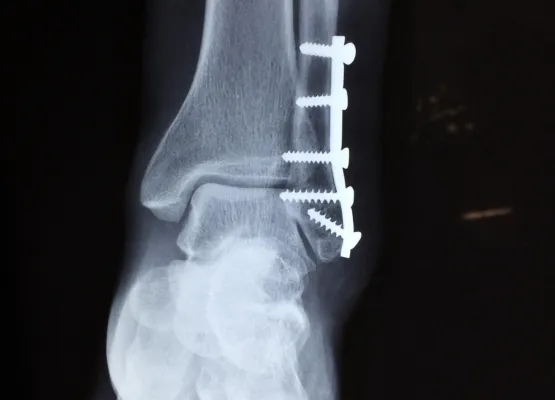

Die Ausrichtung und Fixierung des gebrochenen Körperteils findet unter Schmerzbetäubung statt. Stabilisiert wird mit einem Gips oder mit Nägeln, Platten und Schrauben direkt am Knochen. Bei gebrochenen Zehen, Rippen oder dem Schlüsselbein sorgen meist einfache Verbände für eine sichere Ruhigstellung am Körper. Je nach Art der Fraktur kann die Heilung drei Wochen bis acht Monate dauern. Möglichst früh beginnt der Patient mit Krankengymnastik, um die Beweglichkeit des Körperteils wieder herzustellen.